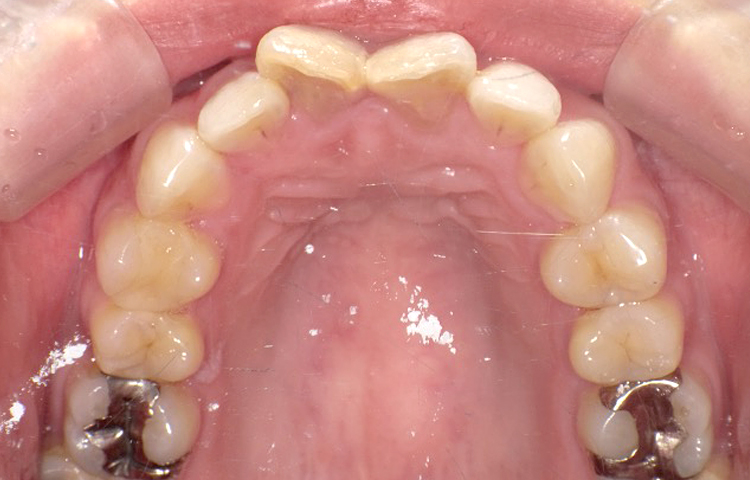

治療前

治療後

| 主訴 | 上の前歯のガタつきが気になるので前歯だけ綺麗にして欲しい |

|---|---|

| 治療 期間 |

約6ヶ月 |

| 治療費 | 165,000円(税込)/調整費用別途 |

| 治療 内容 |

上の前歯部にワイヤーを着けて進めていく、プチ矯正で施術。 |

| 治療の リスク |

見た目を綺麗にする目的で短期間で仕上げる為噛み合わせは矯正しない。 |